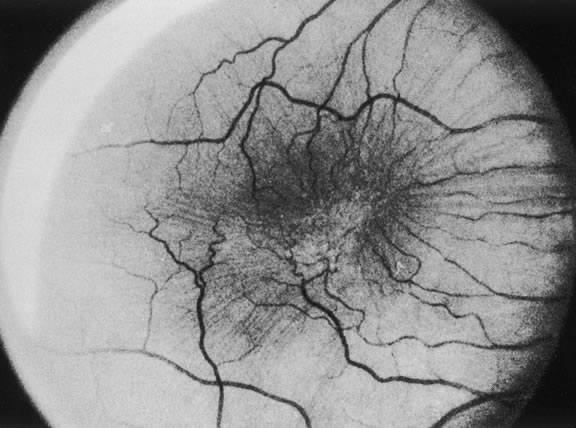

The nature of the adhesion between the vitreous cortex and the ILM is enigmatic. This adhesion is strongest at the optic nerve, the macula, the vitreous base, and retinal vessels. Foos6 demonstrated attachment plaques between Müller's cell cytoplasm and the ILM in the basal and equatorial retina (Fig. 2). Vitreous traction mediated by vitreous fibrils may contribute to these adhesions. These attachment plaques are not present posterior to the equator except where the ILM is thinned in the fovea. This anatomic variation in the fovea region may play a role in the pathogenesis of some of the vitreomacular disorders.

The ILM also thins over major blood vessels. Vitreous strands extend through pores in the ILM to surround the vessels11 and have been termed vitreoretinovascular bands.12 These bands may explain the strong adhesion between the vitreous and retinal vessels.

VITREOUS BASE

The vitreous base is a three-dimensional zone centered on the ora serrata where the vitreous is the most adherent to the retina and pars plana epithelium. It extends approximately 1.5 mm anteriorly to the ora serrata. Nasally, it extends 3.0 mm posterior to the ora and 1.8 mm posterior to the ora temporally. The functional base of the vitreous extends several millimeters into the vitreous body in this region. As the eye ages, the firm attachment of the vitreous base may extend posteriorly for several millimeters. This may lead to localized areas of enhanced vitreoretinal traction and result in retinal tears.

In the vitreous base, collagen fibers are relatively coarse, are numerous, and insert perpendicularly to the retina and pars plana. These fibers consist of collagen fibrils with diameters of 10.8 to 12.4 nm.16 The microscopic detail of the vitreous fibers attachment to the vitreous base varies from anterior to posterior. Anterior to the ora the fibers are less dense than posterior to the ora. Electron microscopic studies by Gartner17 demonstrate that the vitreous fibers have complex interdigitations with the reticular fibrillar materials of the basement membrane of the nonpigmented ciliary epithelium but do not pass between the cells. The anteriormost fibers splay out anteriorly to form the anterior loop of the vitreous base, which is important in the pathogenesis of anterior PVR.18 Posterior to the ora, bundles of vitreous fibrils attach to the ILM. Cords of vitreous collagen insert into gaps between the neuroglia. Gloor and Daicker19 likened this arrangement to Velcro and suggested that this may explain the strong vitreoretinal adhesion of the vitreous base. Cellular elements are also present in the vitreous base. Fibroblast-like cells are present anterior to the ora, and macrophage-like cells are posterior to the ora.17 These cells may play a role in the hypocellular gel contraction that characterizes anterior PVR.